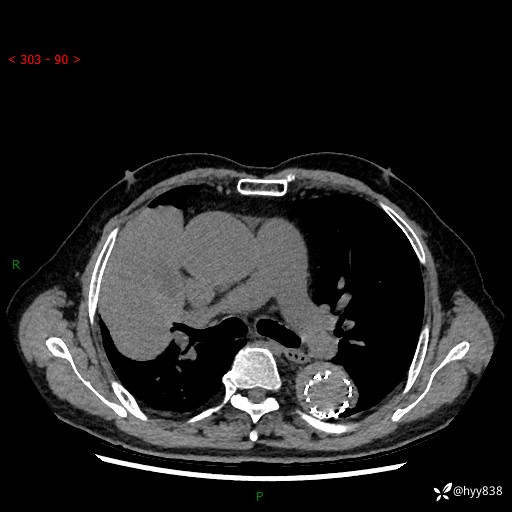

辅助检查:CT

增强动脉期

静脉期